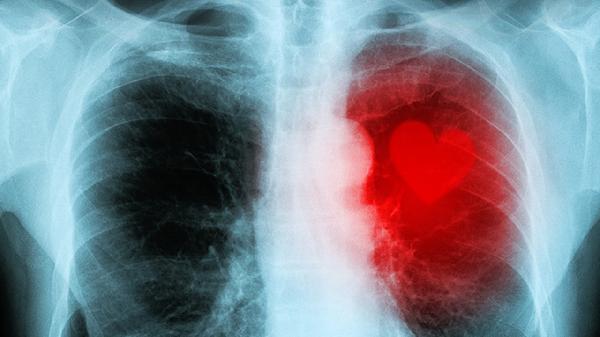

男人吸烟时,若有这四种信号,可能是肺癌的信号,尽早去医院检查

吸烟的人注意了!当你吞云吐雾时,身体可能正在发出求.救信号。别以为咳嗽几声很正常,有些异常表现可能是肺部在"喊救.命"。今天就来聊聊那些容易被老烟枪忽视的危险征兆。